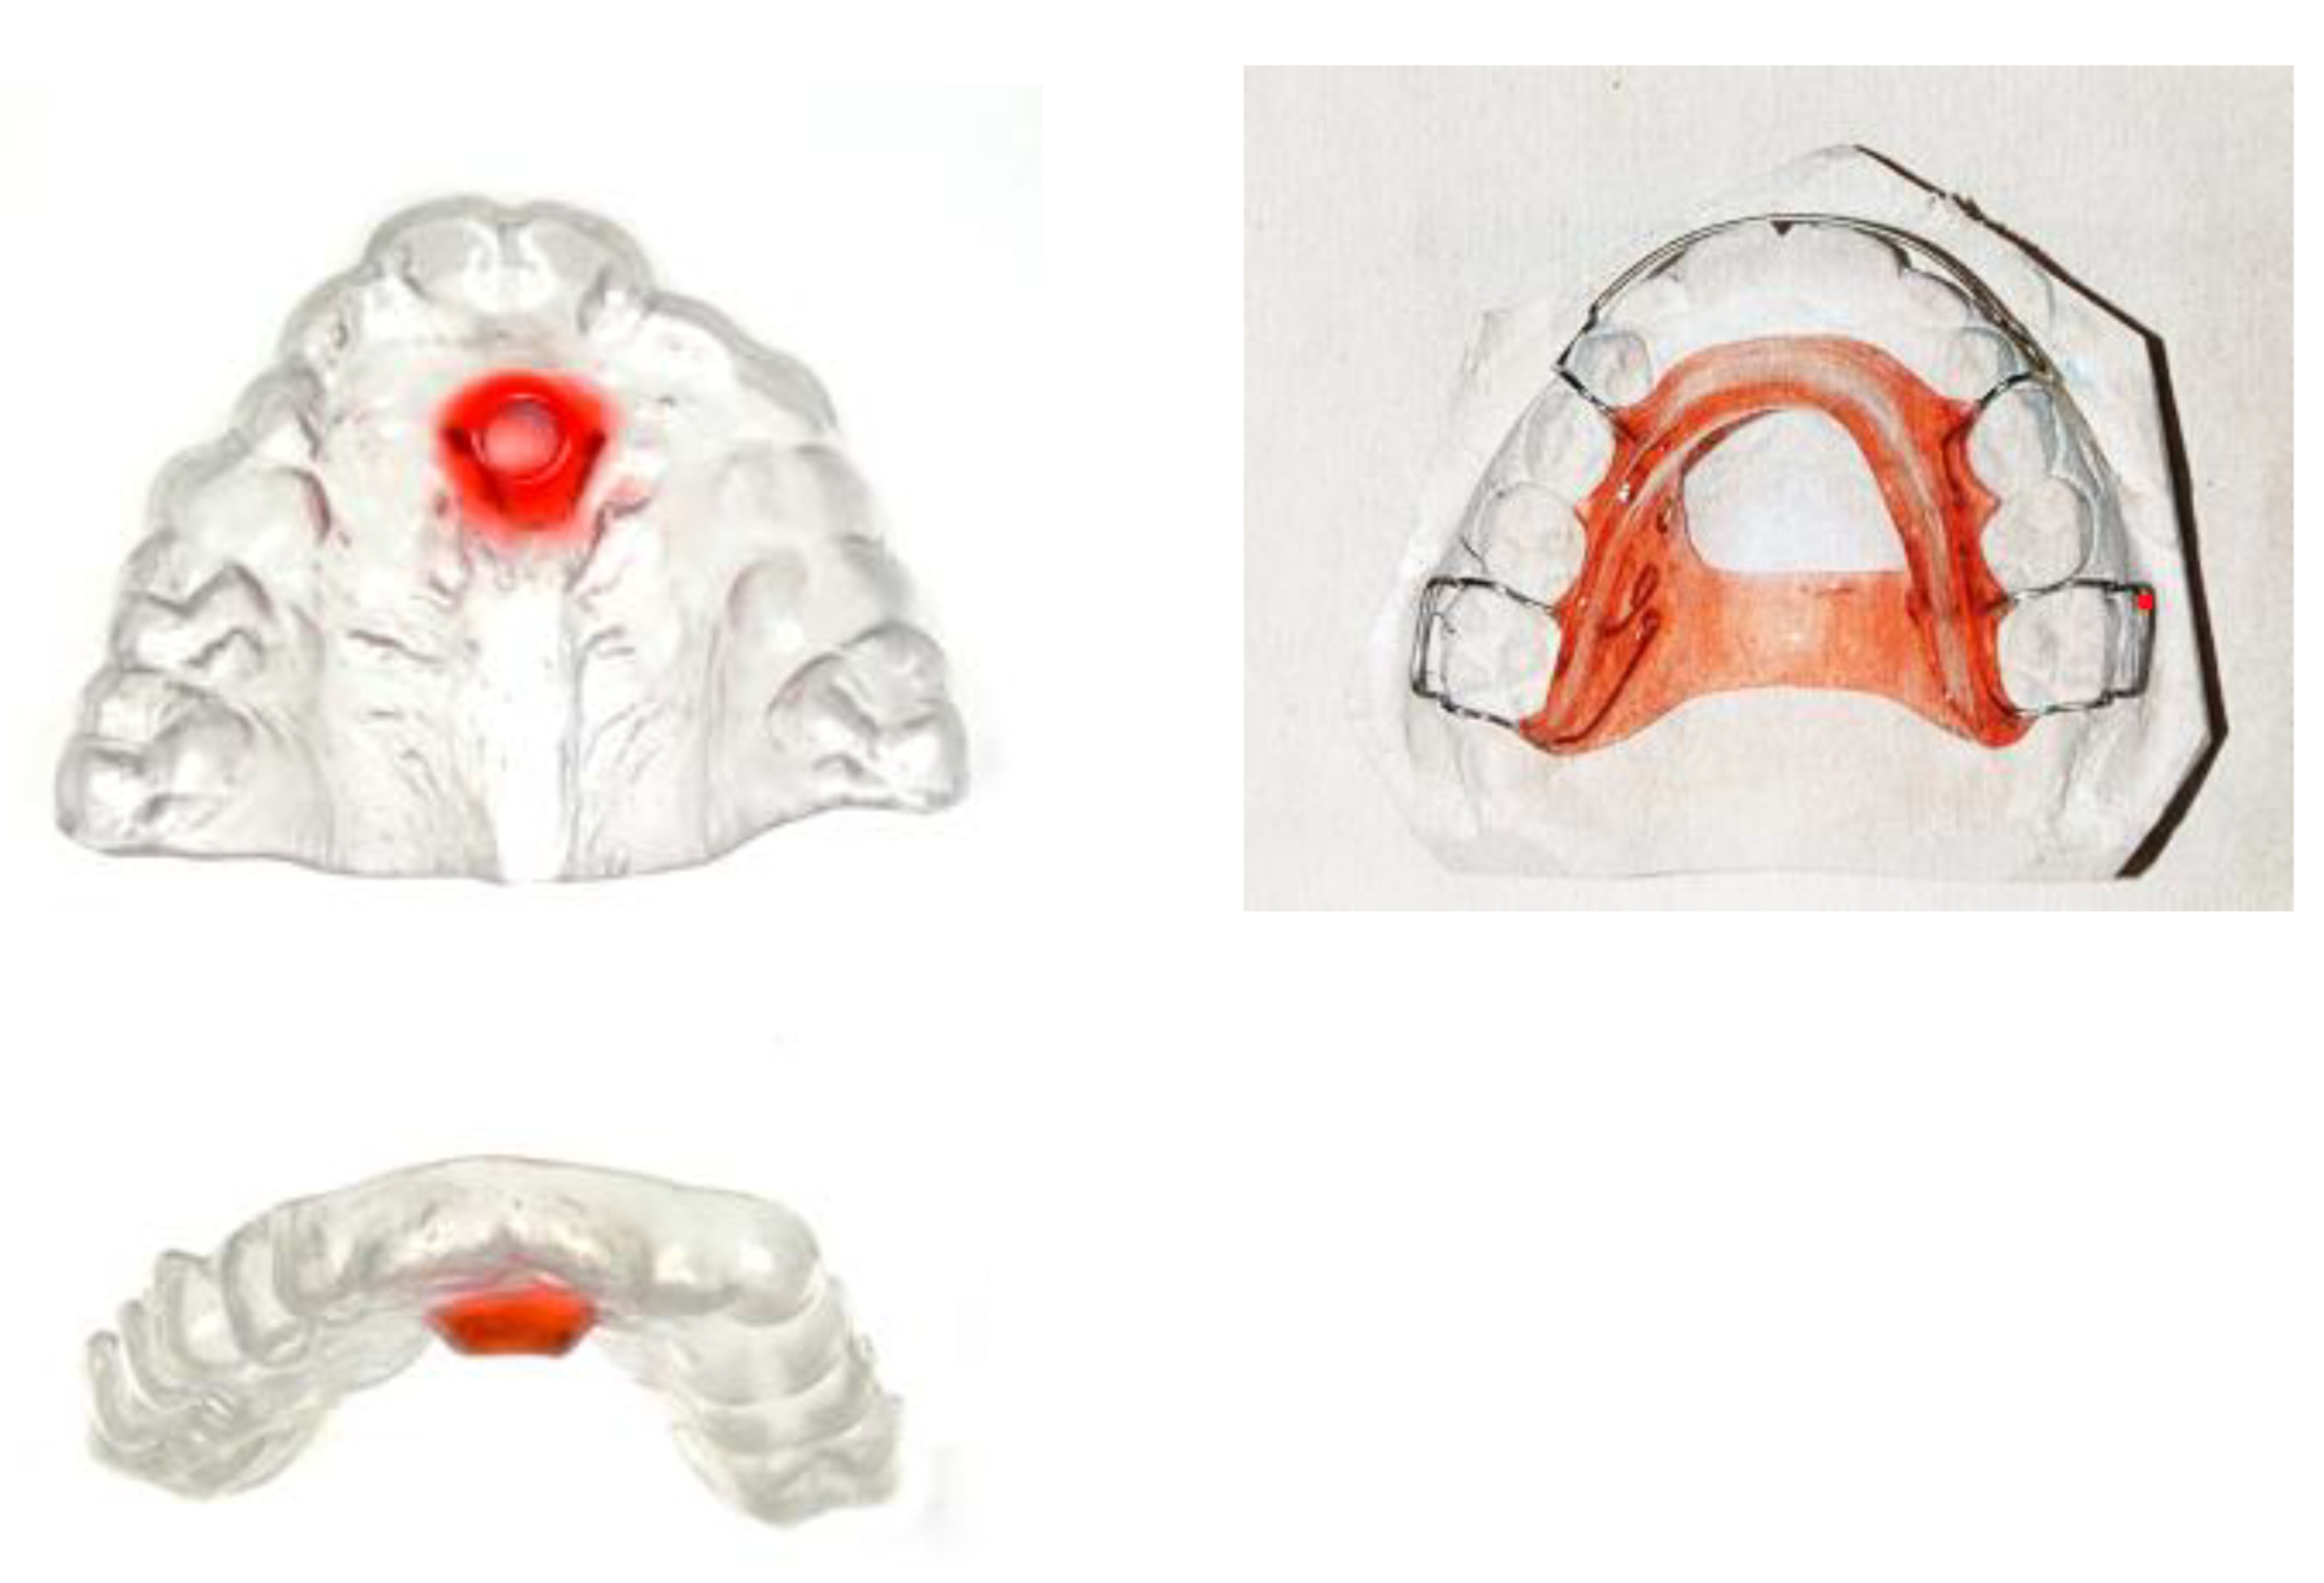

Interceptive functional appliances aim to promote proper tongue posture by stimulating the tongue to rest directly behind the upper incisors, thereby improving habitual tongue positioning (Figure 8).

In a study, an oral device incorporating a tongue stimulation element improved after 12 months of treatment, nasal breathing during sleep, mandibular linear growth, airway morphology, and patient-reported quality of life [112].

Recently, new prefabricated myofunctional devices have been introduced to support oral habit correction and functional training. The “Froggy Mouth®” device has demonstrated efficacy in correcting atypical swallowing patterns and eliminating dysfunctional oral habits [113].

Another prefabricated myofunctional appliance, the “Myobrace®” device, is designed for cessation of habits, occlusal guidance, and orofacial muscle training. This one appears particularly beneficial in managing Class II.1 malocclusion [114].